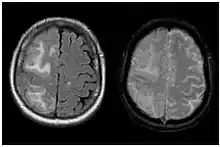

| Two MRI scans demonstrating the difference between ARIA-E (left) and ARIA-H in the parietal region (right) | |